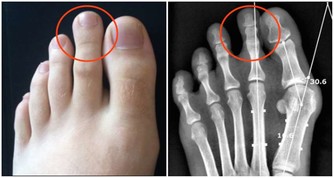

因此,“春捂”應重點做好手腕、腰部、肚臍、小腿及雙腳保暖。

厚褲和厚襪不可過早減去,並常用熱水泡腳,睡覺時下半身蓋厚一點。

此外,初春時節,人們不要換得太快,脫得太早,謹記“上薄下厚”的穿衣原則。

下身的褲子、襪子、鞋子,一定要穿得厚點,暖和點,而上身略減則無大妨礙。